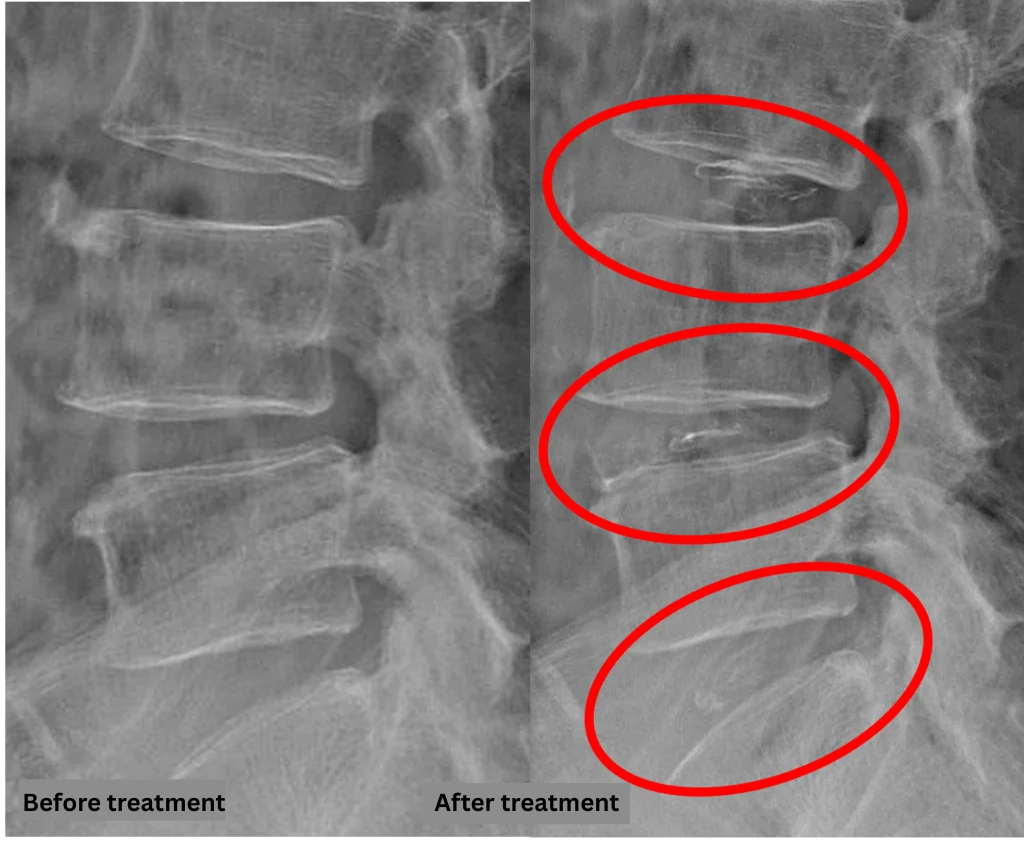

After consulting with the patient, the Cellgel Method was performed on L3/4, 4/5 and 5/s.

The treatment was performed by our administrative director, Dr. Kotera.

The treatment took about 30 minutes.